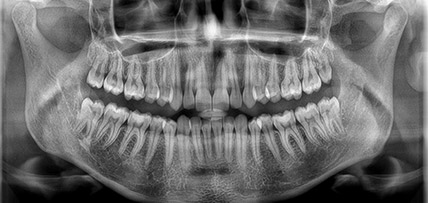

Extraorális (2D) panoráma és teleröntgen

Extraorális (2D) panoráma és teleröntgen felvétel készítés során is több féle felvételt kérhetünk, attól függően, mely terület képezi a vizsgálat tárgyát. Nem feltétlenül szükséges teljes panoráma felvételt készíteni, ha csak néhány fogra vagyunk kíváncsiak, azonban többre, mint amit az intraorális felvételeken szoktunk látni. Ezek a szegmentált felvételek.

Felnőtt panoráma felvétel és ikonja |

Gyermek panoráma felvétel és ikonja |